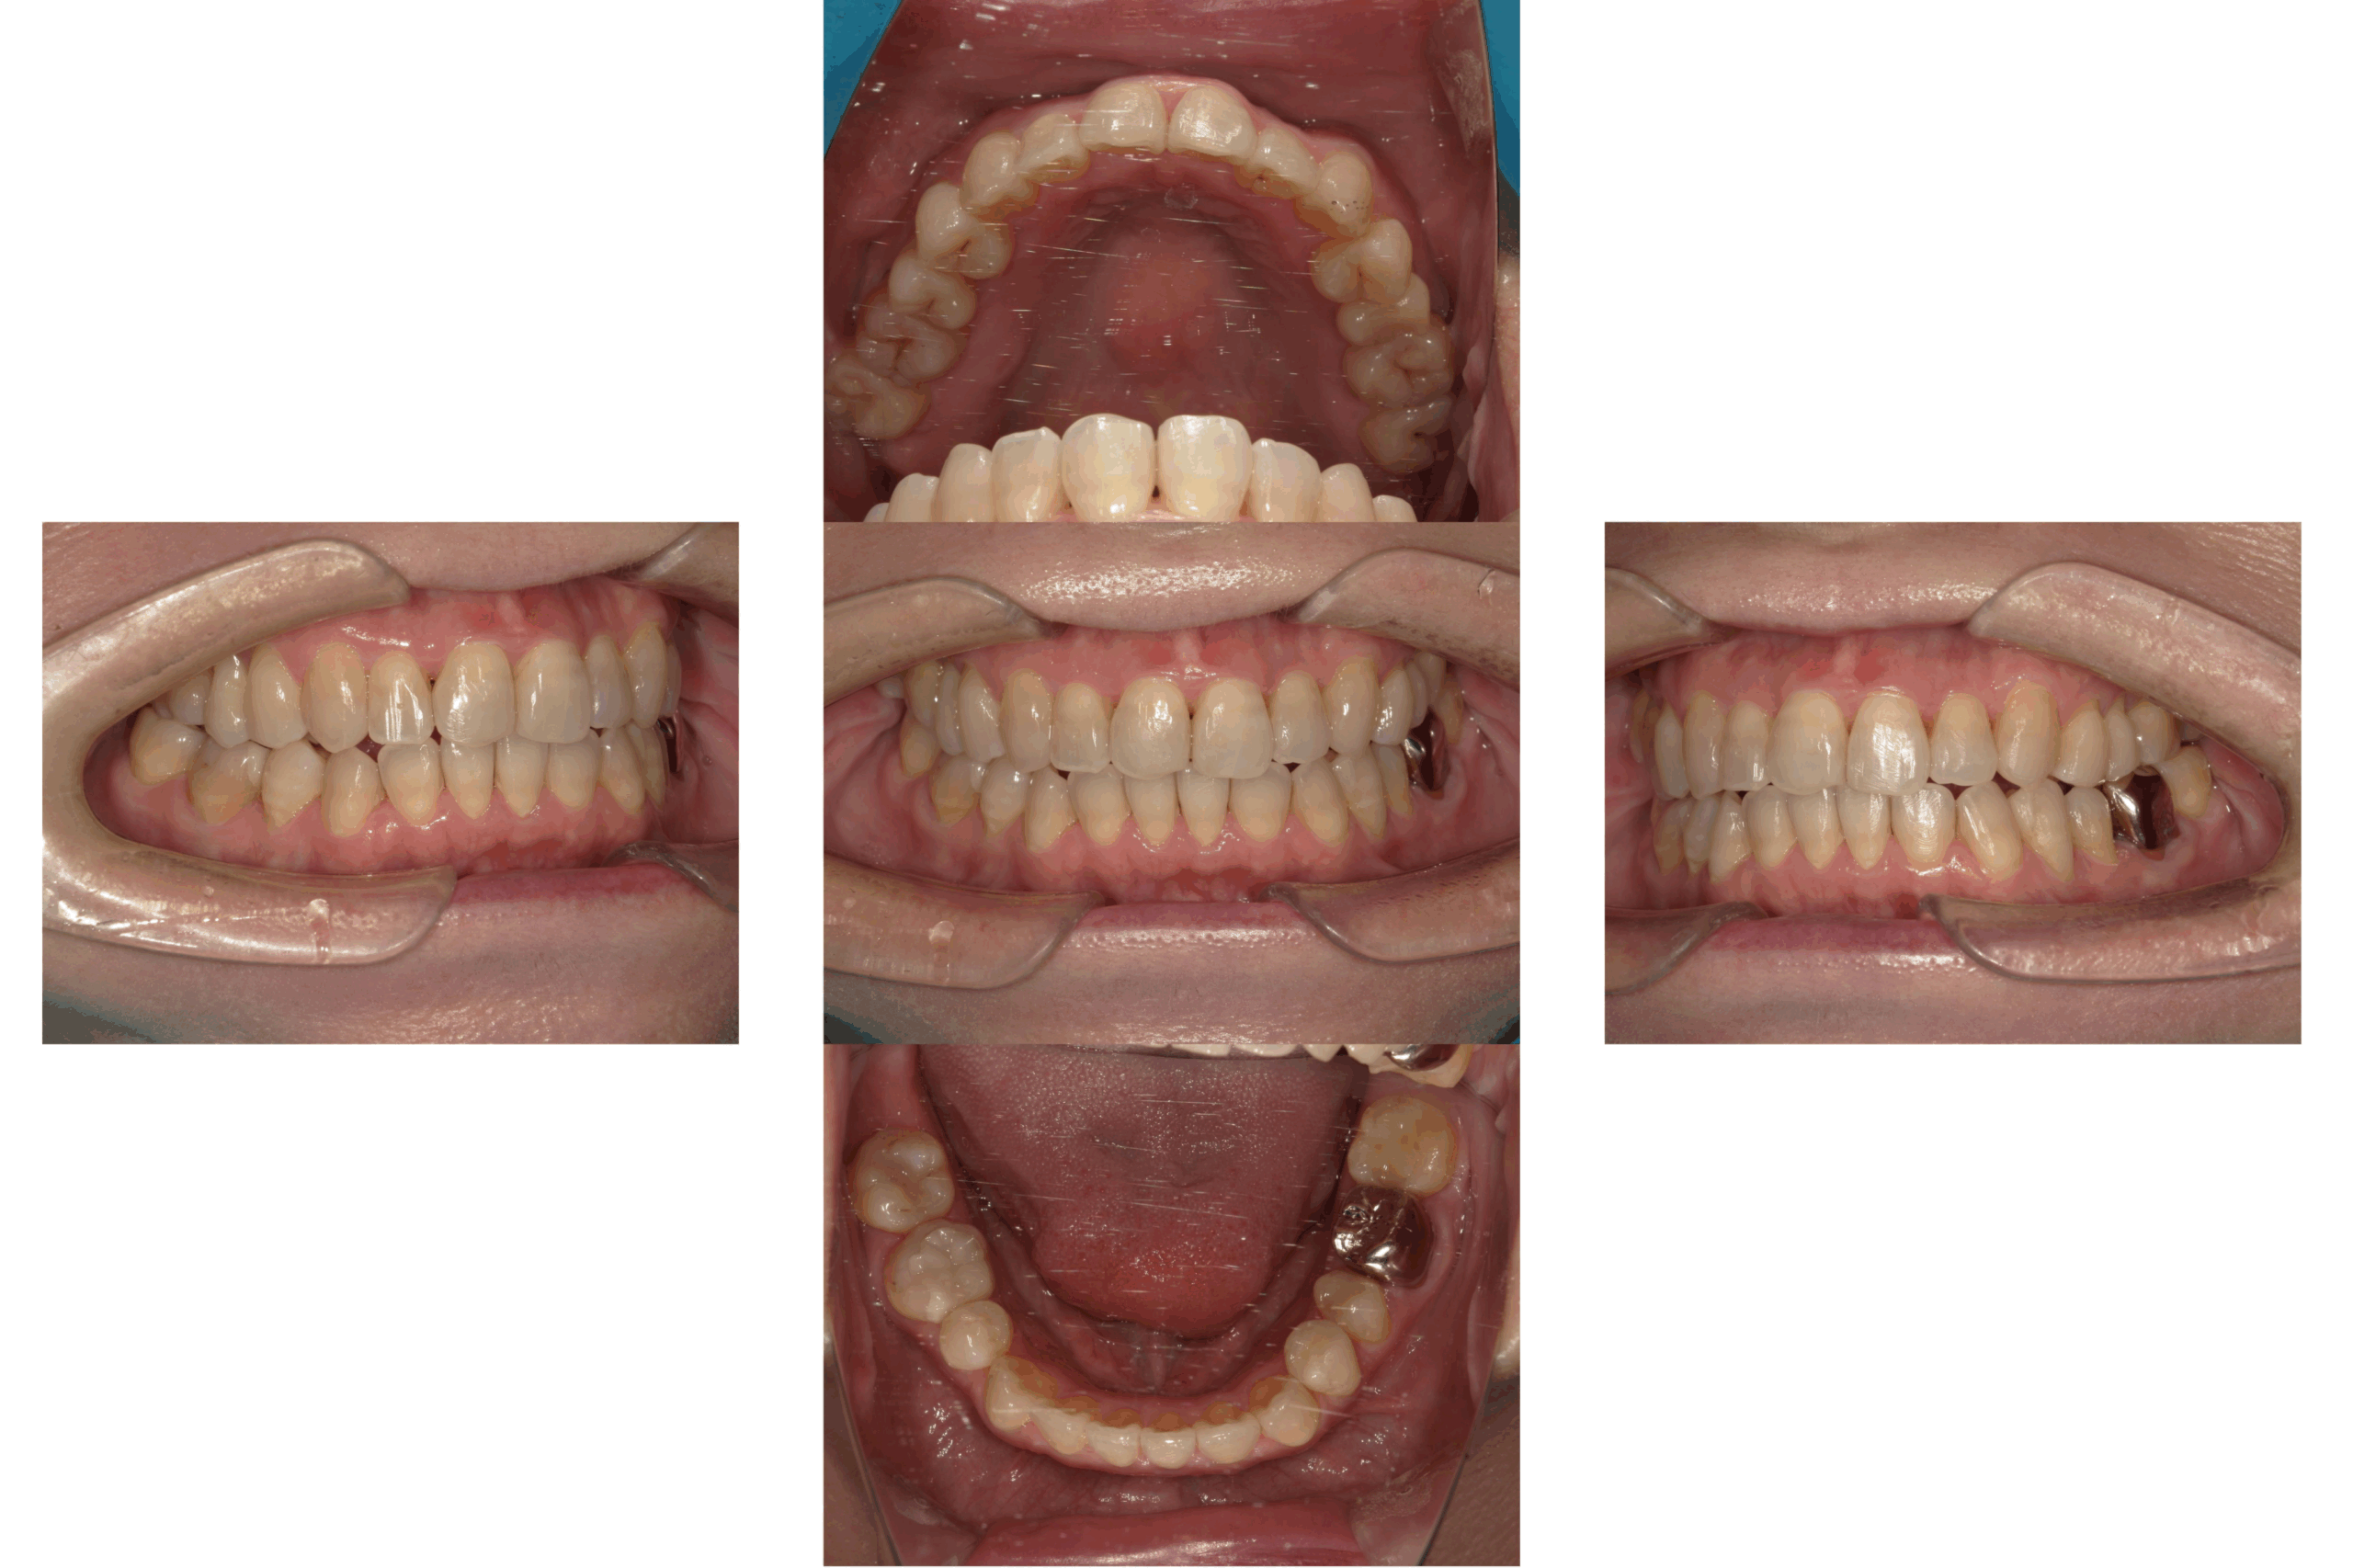

治療前

治療後

| 年齢 | 16歳 |

| 主訴 | 八重歯が気になる。 |

| 治療期間 | 1年 |

| 治療費 | 990,000円(保定装置含む) |

| 概要 | 八重歯が気になり人前であまり笑顔を見せれない。 唇が閉じにくいこともあり、口の中が乾燥していることがある。 |

矯正治療が終わり笑顔にも自信を持つことができ、噛み合わせも整ったことで審美的にも機能的にも満足されています。